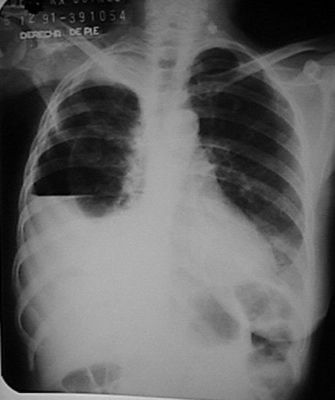

Question

patología que se observa en la radiografía.

Answer

• derrame pleural

• atelectasia

• neumotorax